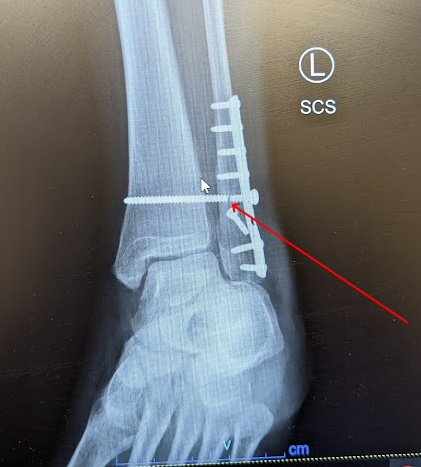

There was snow on the ground. Everything, including the copious amount rocks on the steep surfaces, were slippery. No one else was on the trail and my cellular phone dead. To add insult to injury, the left ankle happened to be my “good” one. I had broken my right ankle several times over the course of my life which lead to a difficult surgery and recovery.

I ended up getting two opinions on the state of my ankle. The orthopedic surgeon who reviewed the X-ray was clear on the need to get into surgery in short order. My prior ankle surgery had to reveal an extreme sensitivity to anesthesia. I knew recovery would be difficult this time. There was a significant amount of metal and titanium screws added to stabilize the fibula and tibia.

Along from the typical difficulties of a recovery, I no longer had my hike to clear my mind. About 6 weeks into recovery, I hit another setback. A titanium screw which was holding the fibula and tibia in stable position broke.